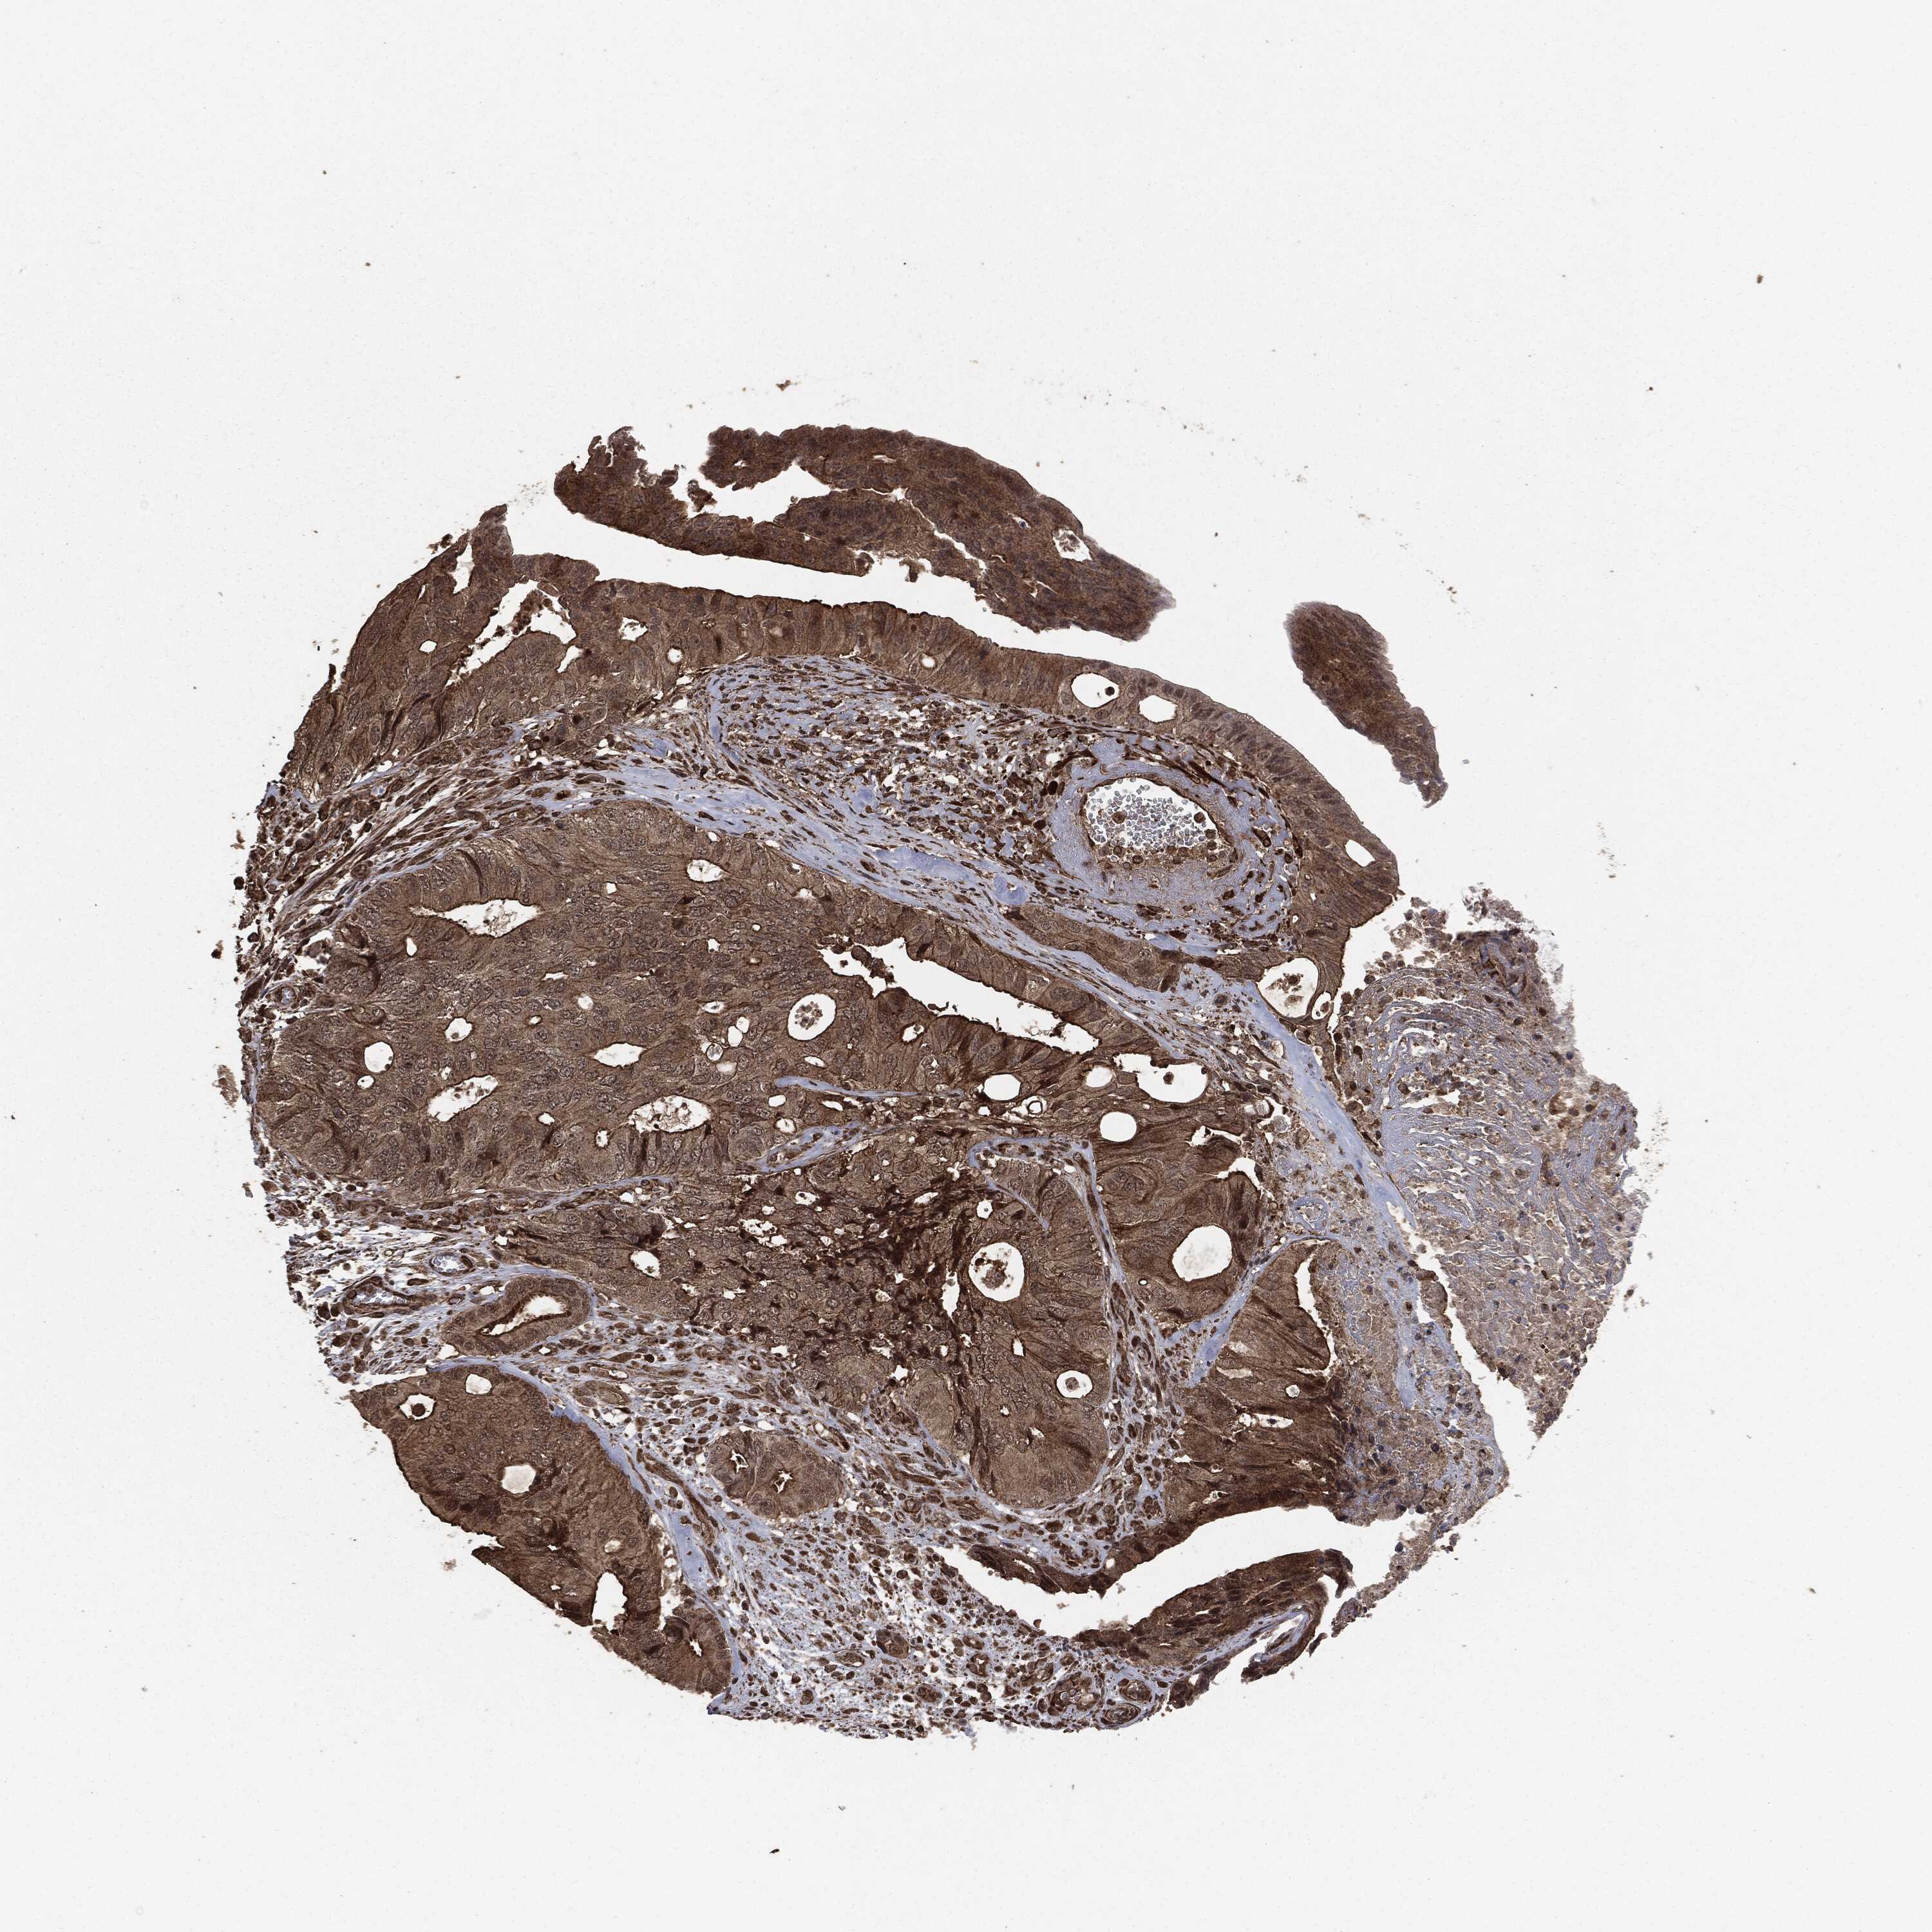

CANCER COLORECTAL CANCER Show tissue menu

Colorectal cancer

Human cancer

Colon adenocarcinoma